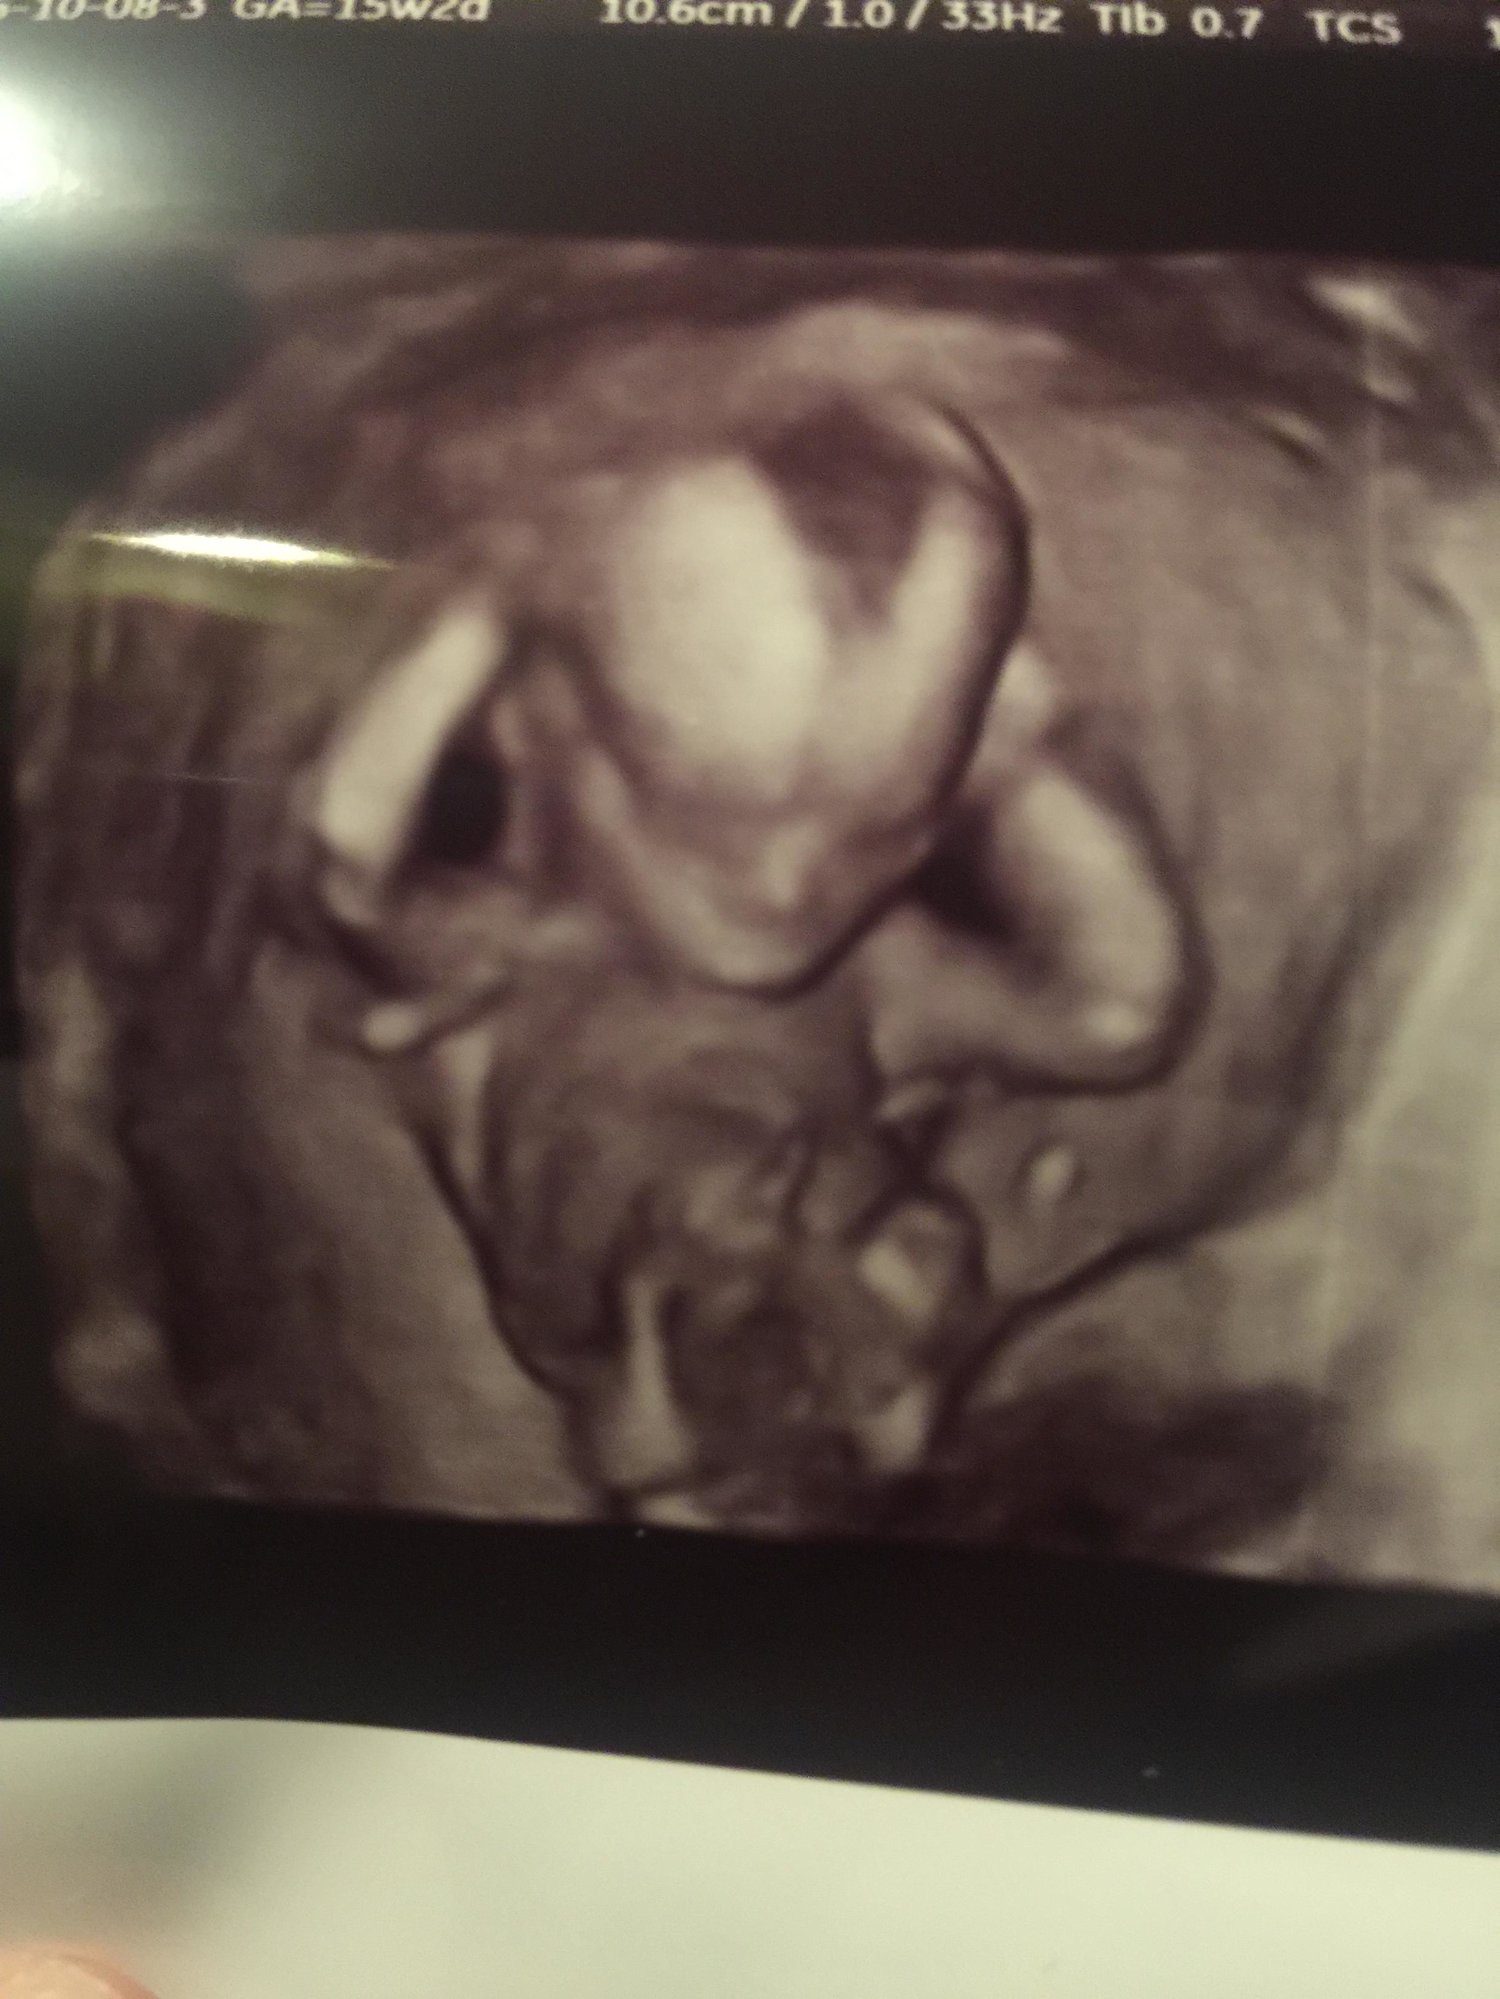

I can't believe I made it!!!! I been so sick and I never thought It would come so fast!!! We have three boys so we would love to have a girl. But to me I just want a health baby!!! I have had so much anxiety about something going wrong so I just can't wait to see him or her:) wish me luck that today will go fast cause my app is not till 3:)